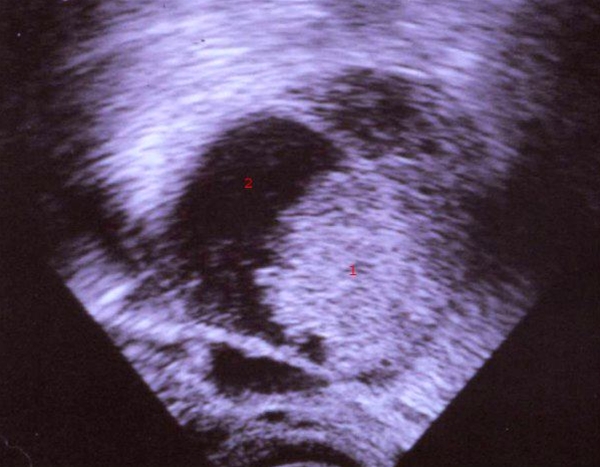

Ultralydskanning viser svulst i livmoderen

endometroid adenocarcinom-ultralyd

1. Knude (tumor) der kan være ondartet i livmoderen

2. Livmoderhulen